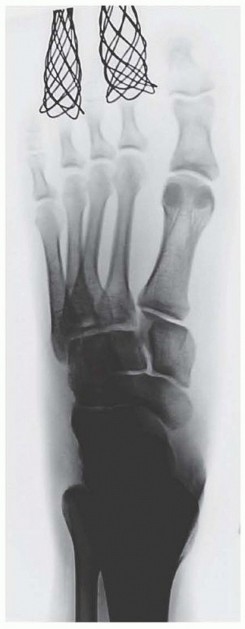

Computed tomography (CT) scanning may also be beneficial in the instance of a subtle Lisfranc injury, particularly in a polytrauma patient or a patient with multiple extremity injuries that preclude weight-bearing radiographs, and in delineating proximal fracture line extension into the navicular, cuboid, or cuneiforms (

FIG 4

).

• CT scan showing displacement through second tarsometatarsal and intercuneiform articulations (

A

) and intra-articular fractures of navicular and cuboid (

B

,

black arrows

) in a different patient.